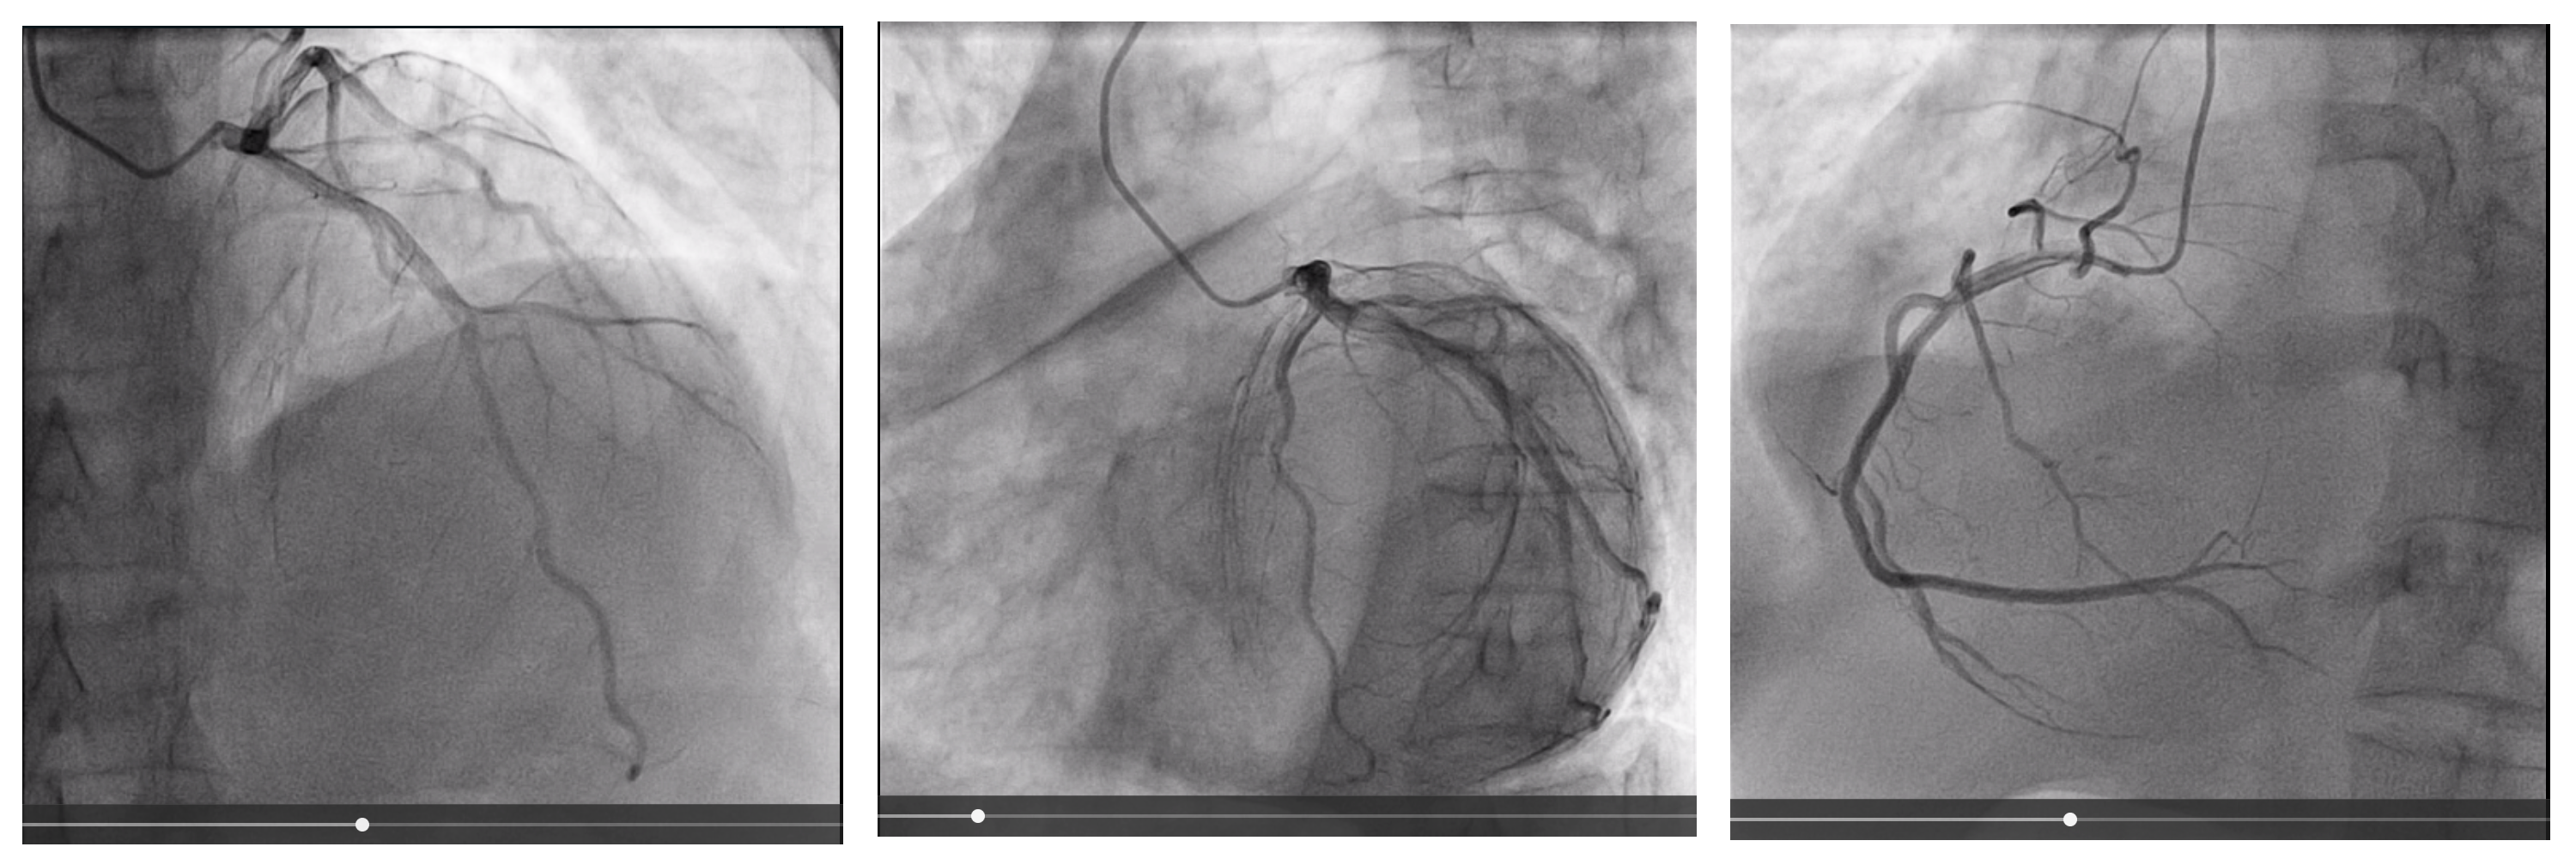

Coronary evaluation

cag.png